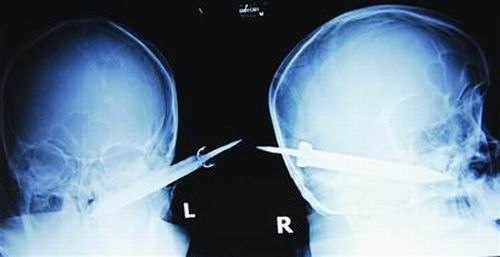

经过检查,医生说这把长有10厘米左右的刀,从右耳窝上前方直接刺进了鼻腔,离颌内大动脉很近,刀卡在了骨头中,要取出这把刀最怕大出血,万幸的是这把三棱刀并没有伤及大脑。

截至昨晚11时30分,患者头部刀经手术已取出,生命体征平稳。(芮潇潇)